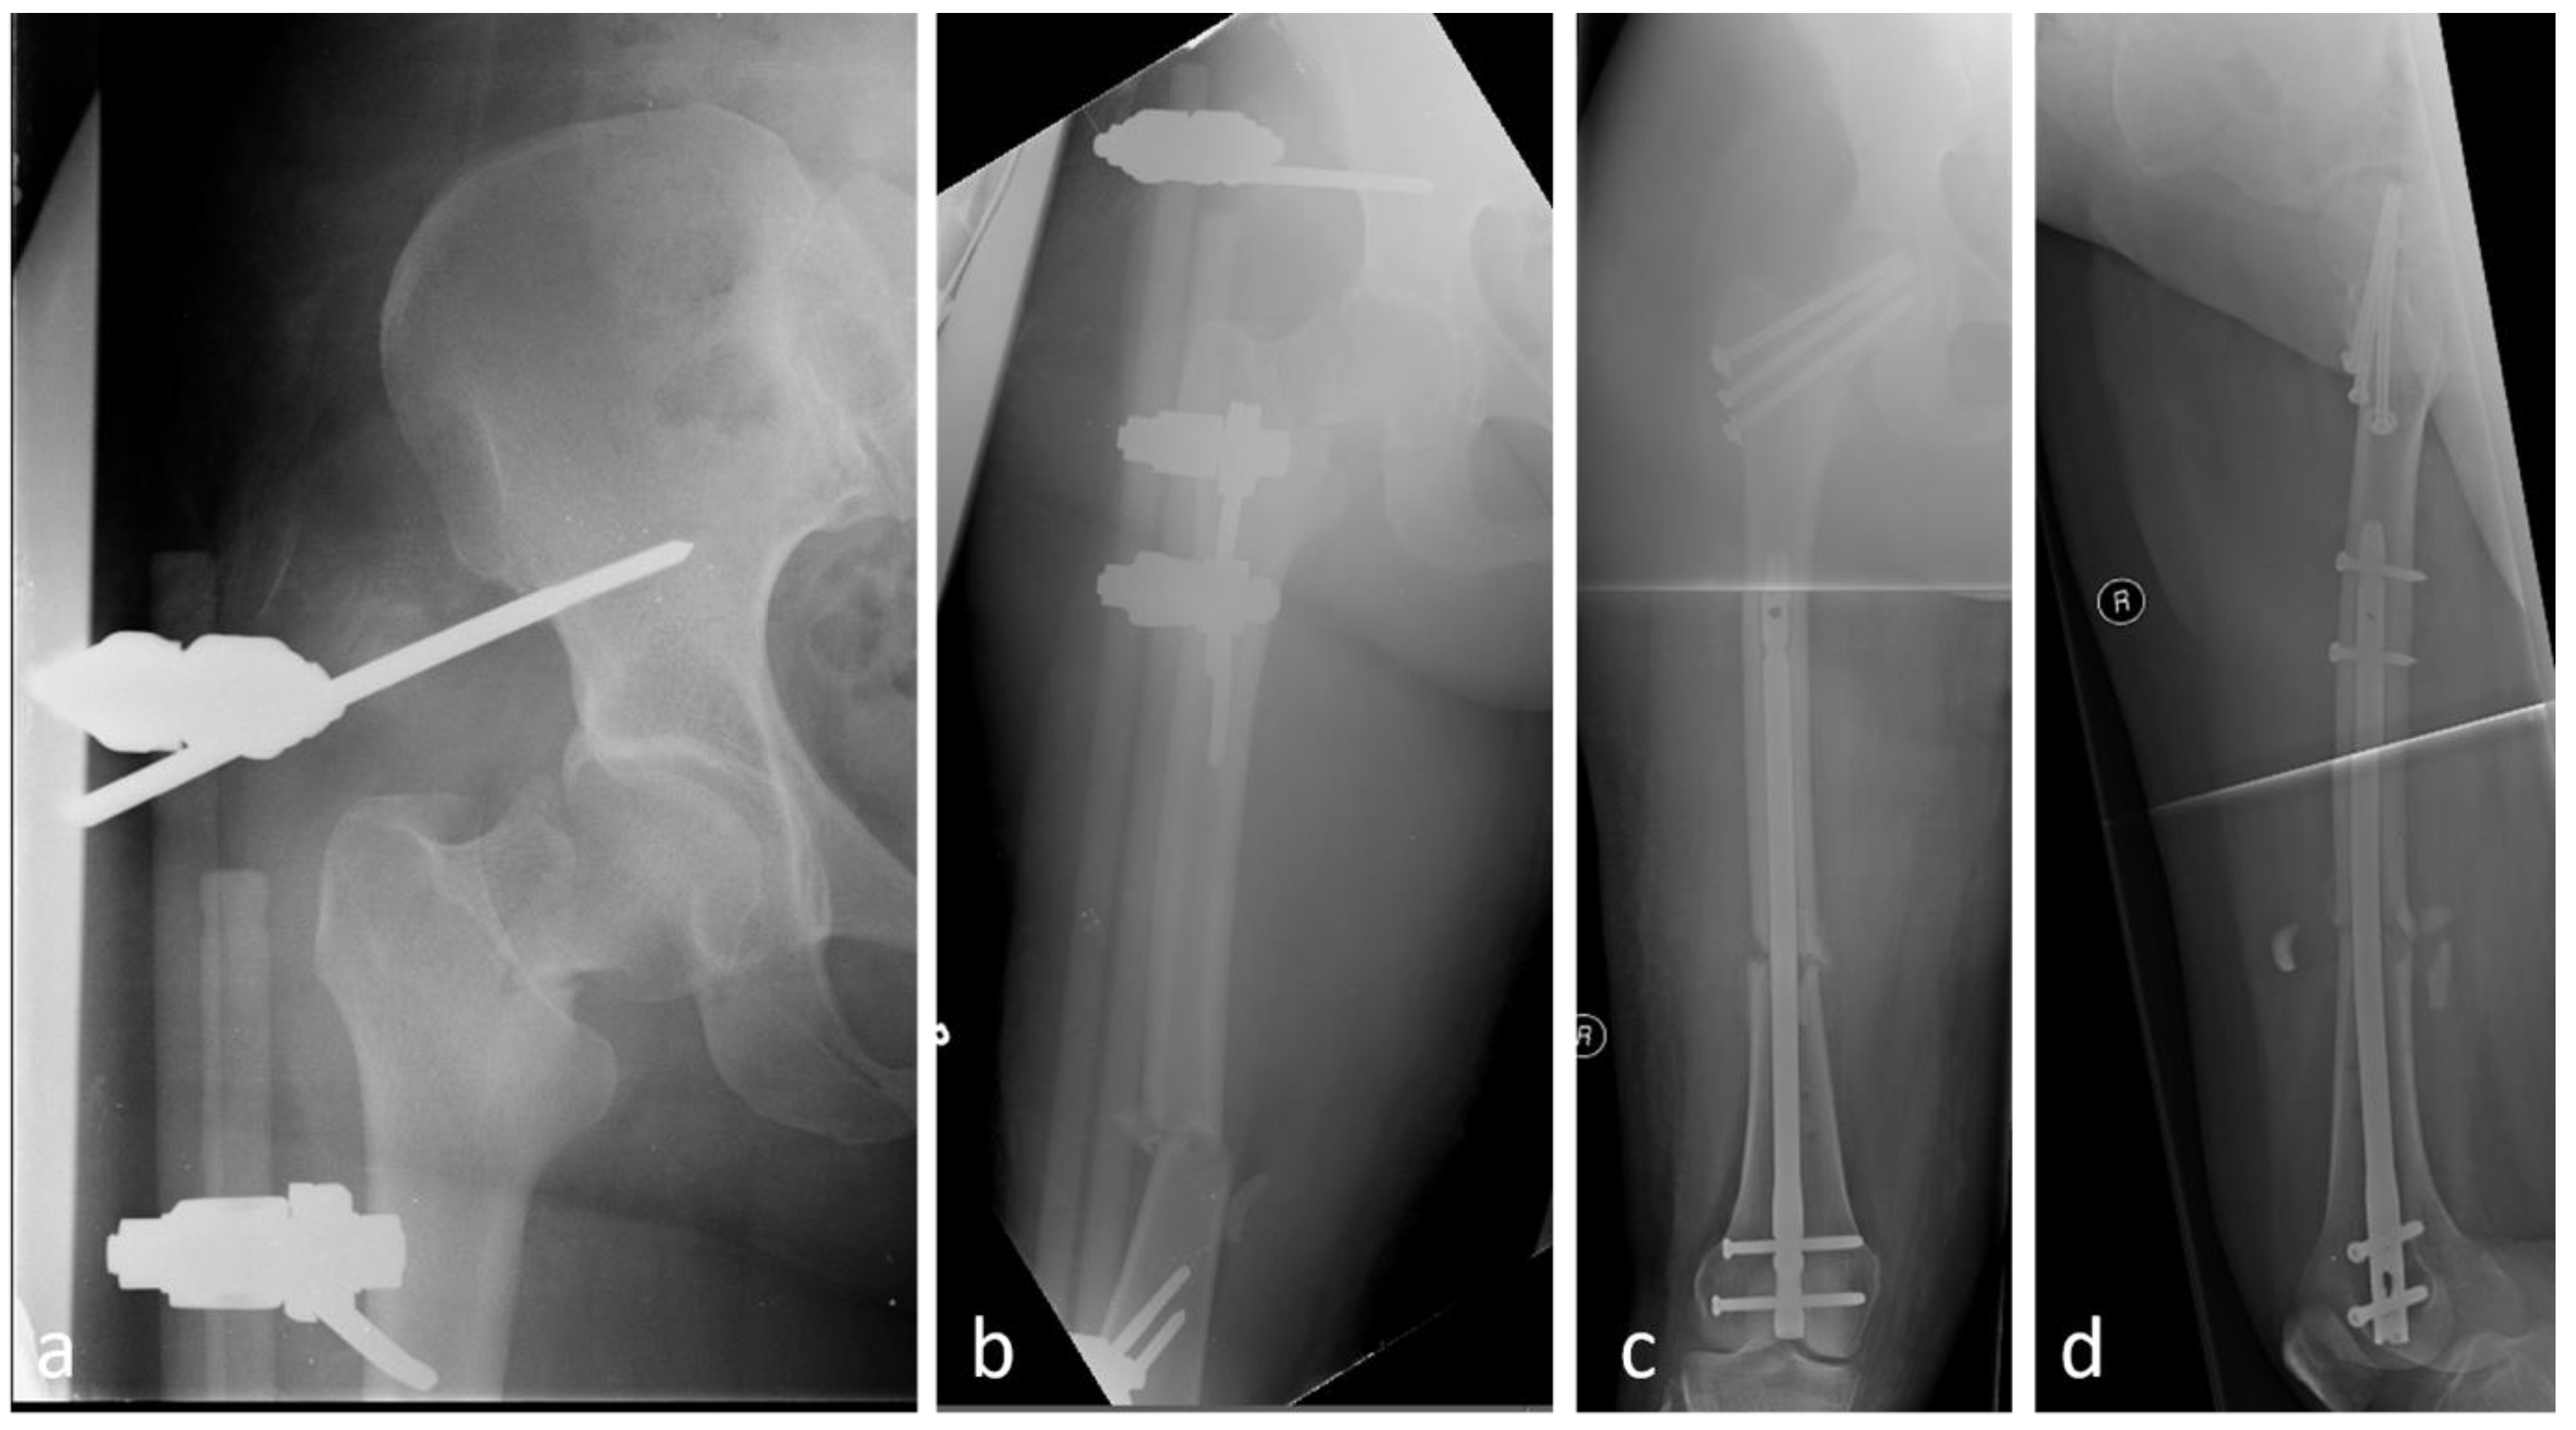

5.3. Reconstruction With or Without Additional Cables and Plates

5.5. Long Cephalomedullary Nail vs. Short Cephalomedullary Nail

- Dietze, C.; Brand, A.; Friederichs, J.; Stuby, F.; Schneidmueller, D.; von Rüden, C. Results of revision intramedullary nailing with and without auxillary plate in aseptic trochanteric and subtrochanteric nonunion. Eur. J. Trauma Emerg. Surg. 2022, 48, 1905–1911. [Google Scholar] [CrossRef] [PubMed]